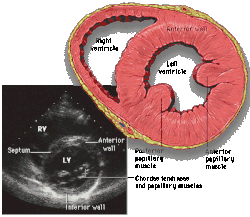

Parasternal short axis (PSAX)

This view is obtained in the same window as the parasternal long, but with the probe rotated 90°. In this view, the aortic valve is seen in cross-section with the right ventricular inflow & outflow tracts visible with the tricuspid valve as well. Pulmonary valve is not visible in this view. Both the right and left atria are visible.

The standard PSAX view is at the level of the aortic valve, but moving the probe along the long-axis can review the LV outflow tract, LV at the base, and LV at the midsection.

Structures visible:

- Aortic valve in short-axis

- Aortic valve dysfunction, aortic sclerosis/stenosis

- Tricuspid valve in long-axis

- Pulmonary valve in long-axis

- Right ventricle, including inflow and outflow tracts

- Left ventricle in short-axis

- Closer to the base can reveal the left ventricular outflow tract

- At the level of the base can show the movement of the mitral valve leaflets in short-axis

- At the level of mid-LV can show papillary muscles